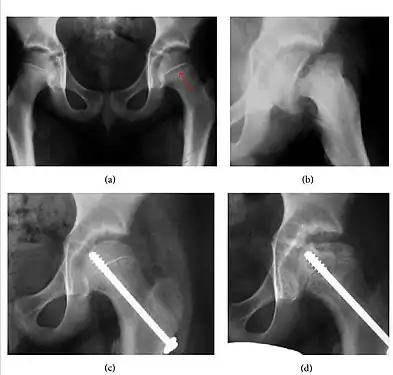

- Slipped capital femoral epiphyses (SCFE)

Slipped capital femoral epiphyses (SCFE) usually affect 11- to 14-year-old adolescents (Figure 4). Radiographs may show widening and irregularity of the physis and posterior inferior displacement of the capital femoral epiphysis. On the AP view Klein’s line, tangent to the lateral aspect of the femoral neck, does not intersect the femoral head indicating that it is displaced. SCFE may compromise the blood supply to the femoral head and cause avascular necrosis, mainly when there is instability between the fragments.[1]

Figure 4: (a) X-ray of a 10-year-old child with left hip pain. It was considered normal at emergency despite the widening of the left physis (arrow). Two weeks later epiphysiolysis was evident (b). Despite appropriate surgical reduction (c) osteonecrosis developed and femoral head collapsed 1 month later (d).[1]